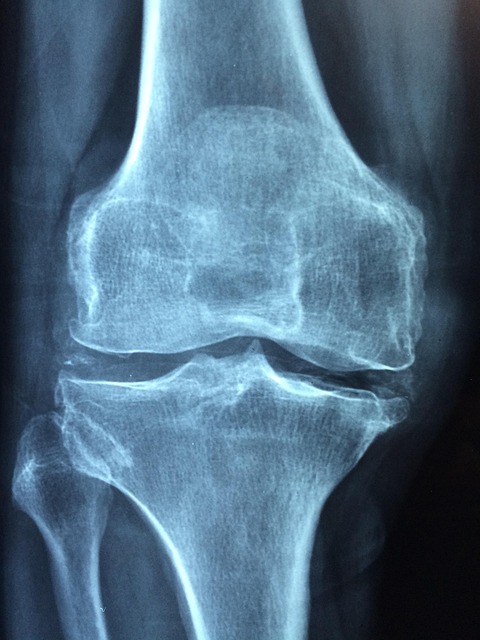

1기 관절염은 연골 손상이 시작된 초기 단계로, X-ray 검사에서 큰 변화는 보이지 않지만 환자는 뚜렷한 통증이나 뻣뻣함을 느끼기 시작합니다.무릎 관절염 1기 증상 초기 통증이 있으신 분들은 아래 통증 완화 방법을 아래에서 확인하시기 바랍니다.

2025년 현재, 무릎 관절염 진단은 단순 X-ray 외에도 MRI, 초음파, 인공지능(AI) 관절 분석 프로그램이 적극 활용되고 있습니다.

특히 AI 진단 보조 시스템은 환자의 보행 패턴, 무릎 압력 분포를 분석해 조기 관절염 여부를 더 정확하게 판별할 수 있습니다.

5. 병원 진단과 검사 방법

- X-ray : 관절 간격 변화 확인

- MRI : 연골 손상 여부 세밀 분석

- AI 보행 분석(2025년 도입 확대) : 무릎 하중 불균형 확인